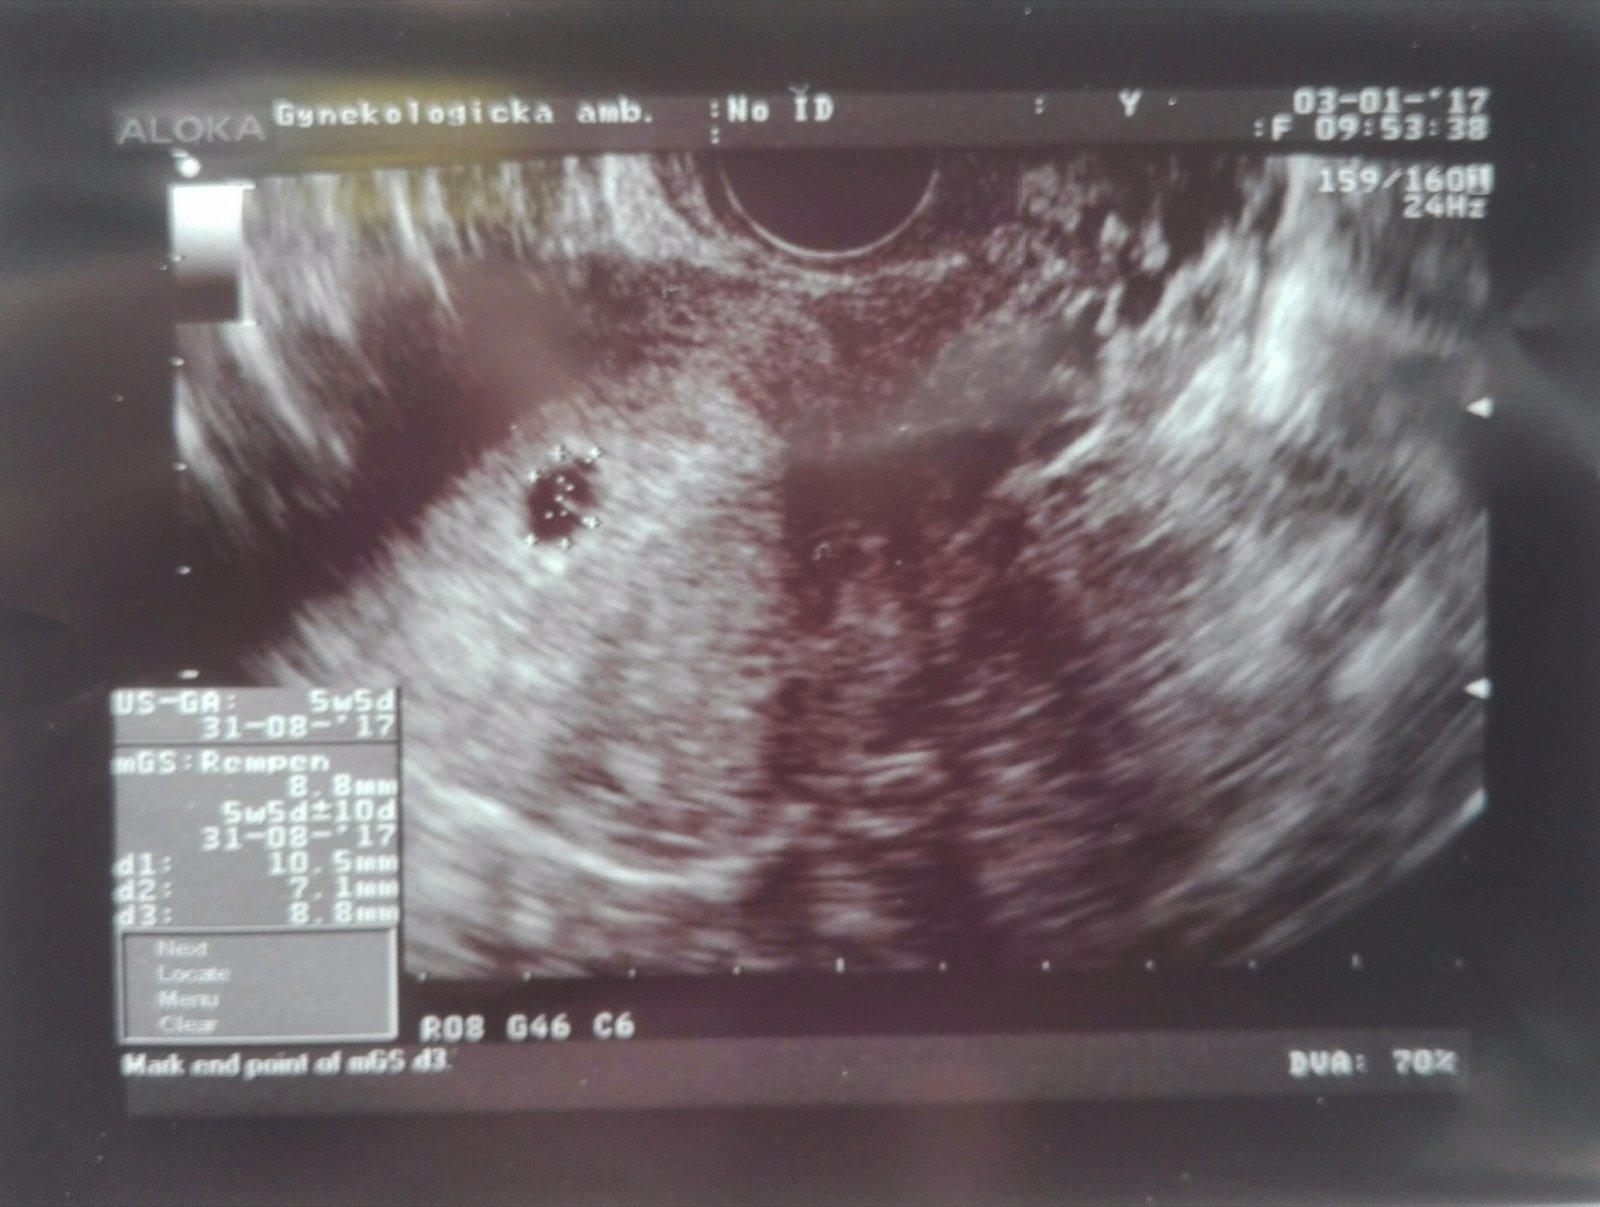

Náš duch na teste je nádherná fazulka. ☺ Drobček 5tt+5d ☺